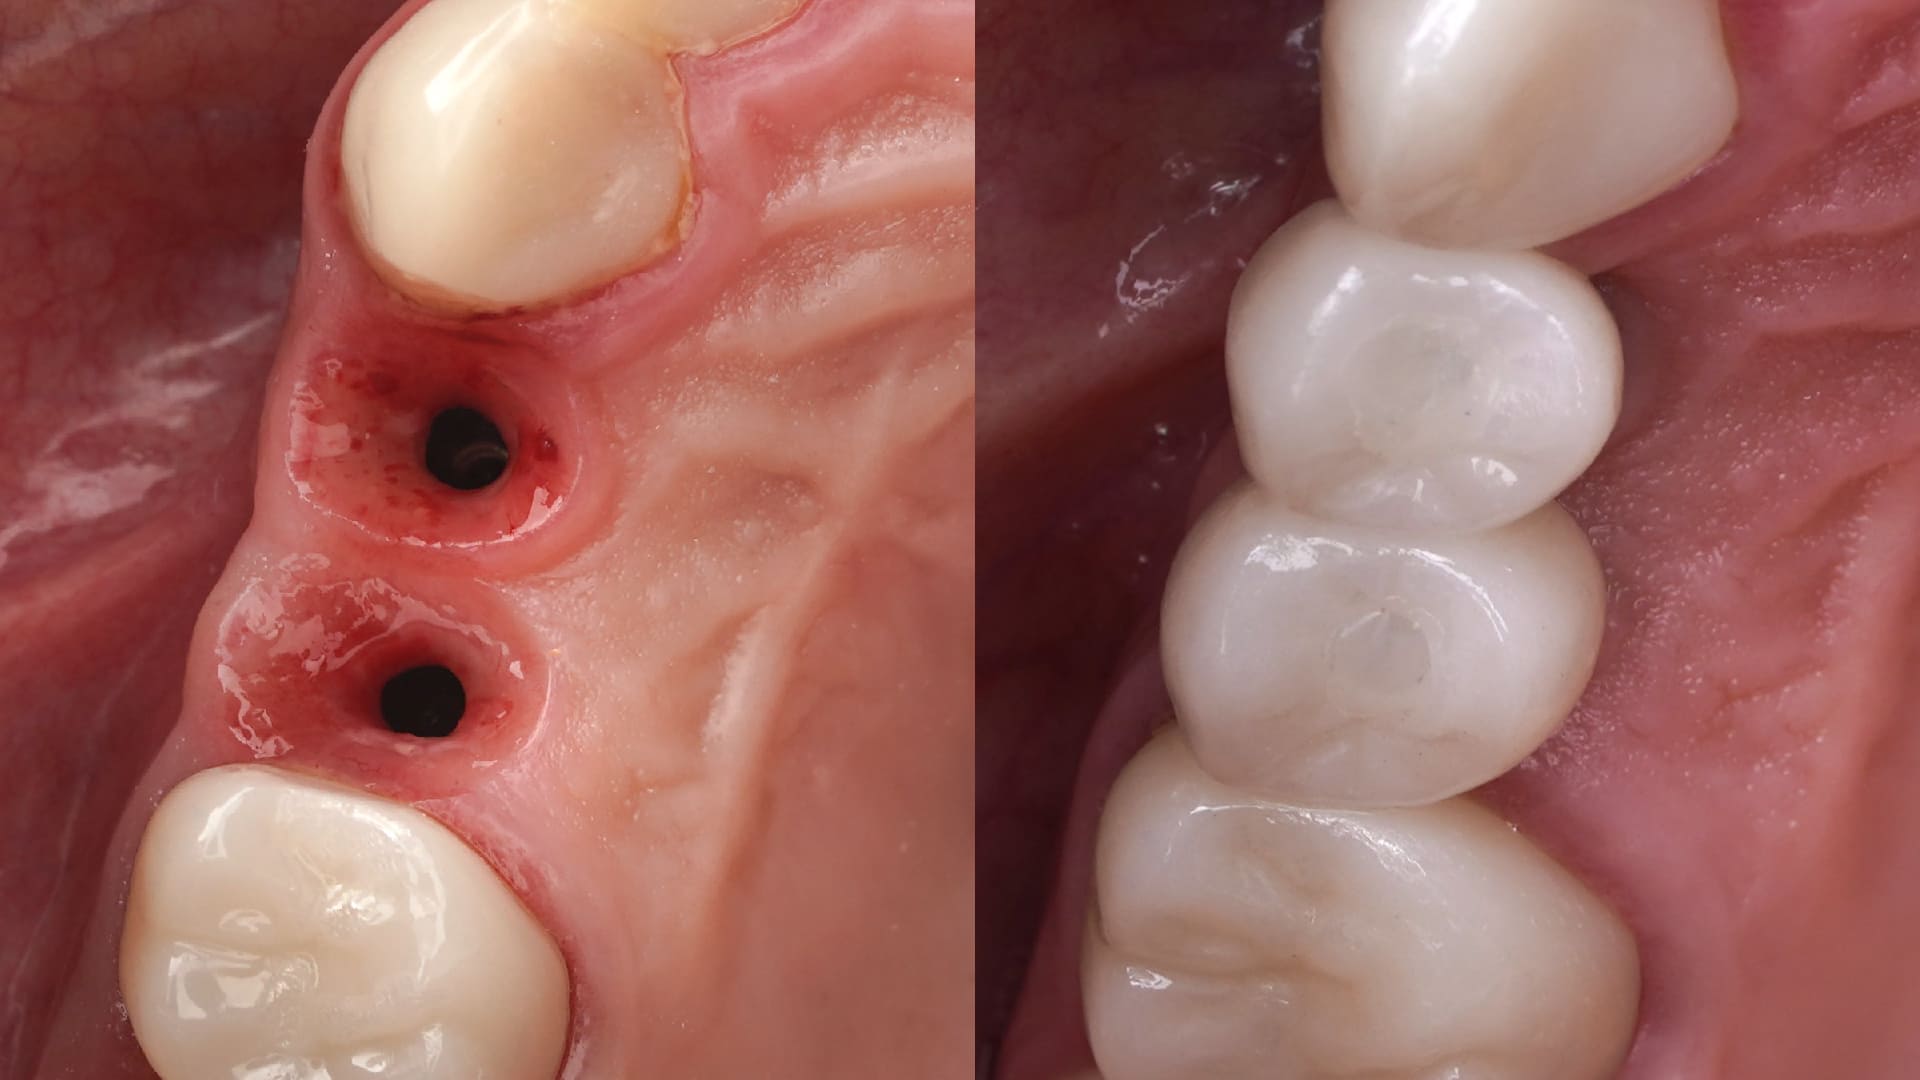

Posterior Immediate Implants.

Customized healing in the posterior sites

CLINICAL CASES